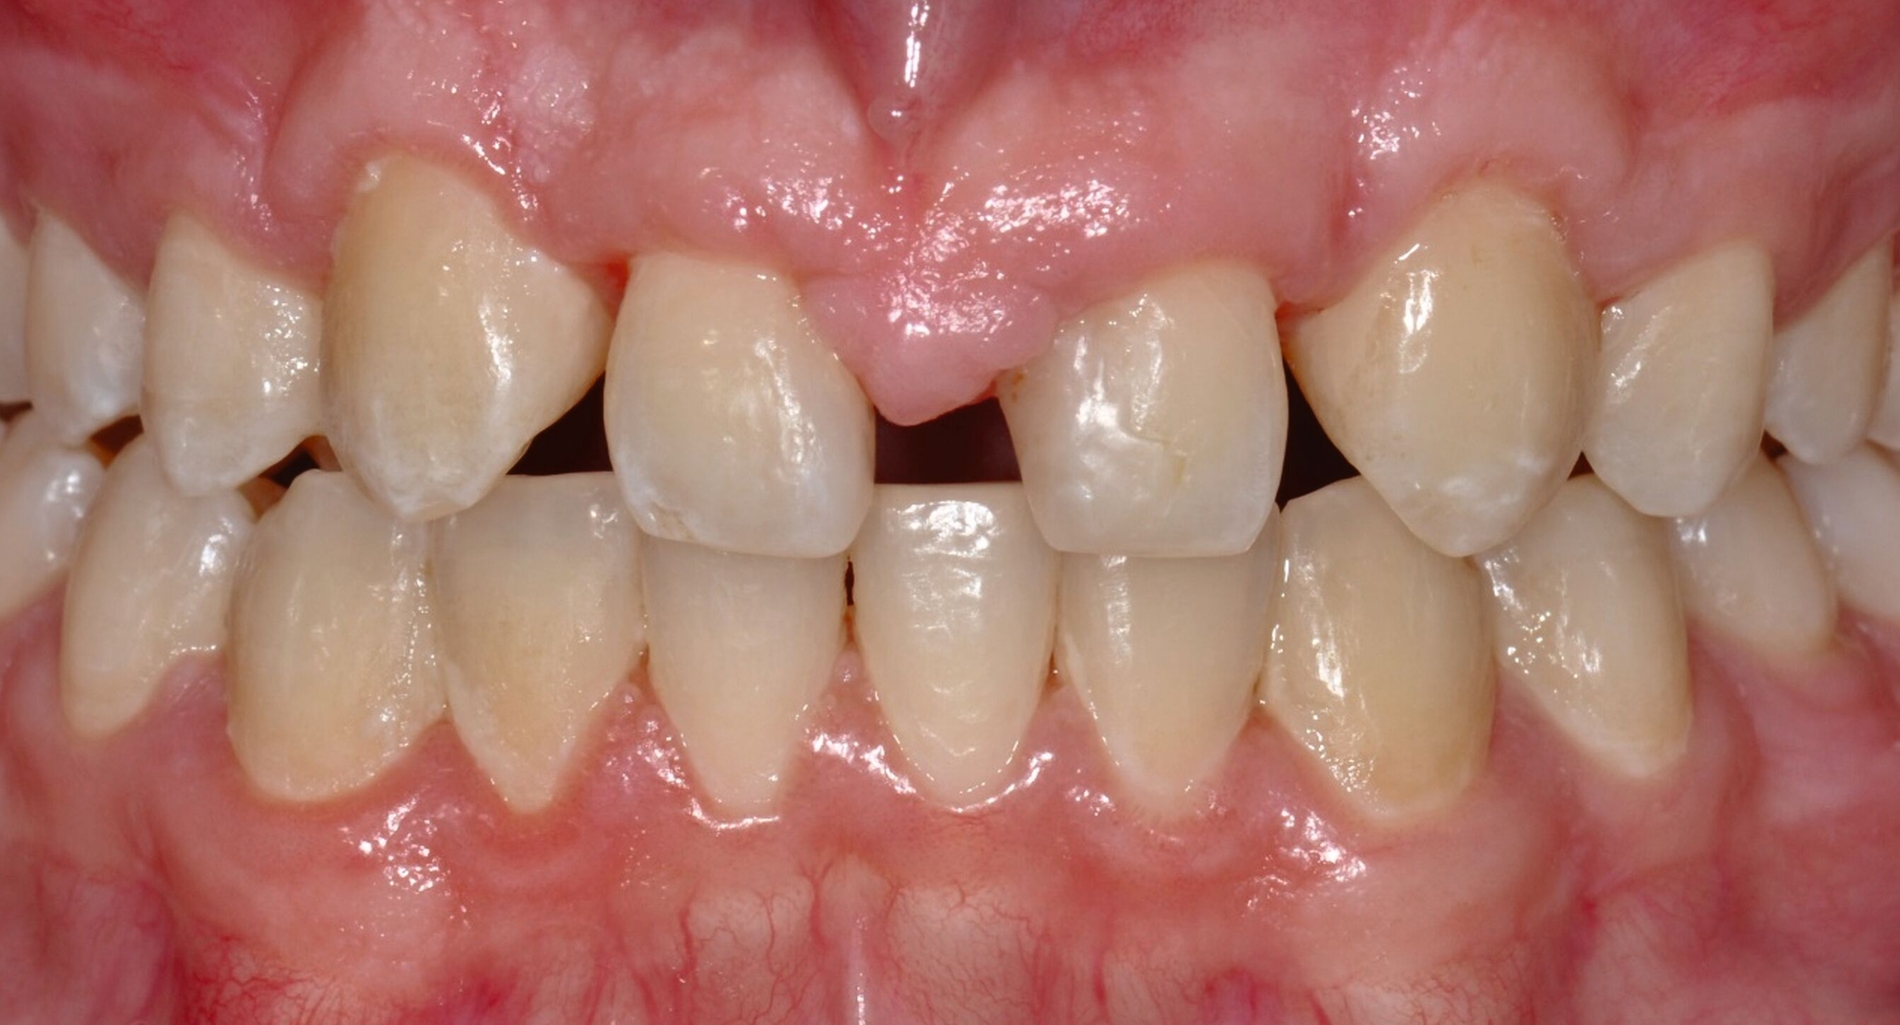

Bei der Erstvorstellung zeigt der Patient ein ausgeprägtes Diastema mediale sowie Restlücken und Asymmetrien im Oberkieferfrontzahnbereich nach kieferorthopädischer Therapie alio loco (Abbildung 1). Aufgrund mangelnder Adhärenz konnten nicht alle kieferorthopädischen Behandlungsziele erreicht werden, was insbesondere aus ästhetischer Sicht Herausforderungen für den restaurativen Lückenschluss mit sich bringt. Erschwerende Faktoren sind die Verschiebung der Mittellinie, die Achsenneigung der Zähne 13, 12, 22 und 23 sowie die inhomogene Lückenverteilung mit ungleich verteilten Lückengrößen (Abbildung 2). Eine erneute kieferorthopädische Korrektur lehnt der Patient allerdings ab. Subjektiv empfindet er insbesondere das kindliche Erscheinungsbild der lückig stehenden, kurz und klein wirkenden seitlichen Schneidezähne als störend. Ziele der Behandlung sind eine präventionsorientierte, ästhetisch-funktionale Rehabilitation des Oberkieferfrontzahnbereichs und eine Harmonisierung des dentofazialen Erscheinungsbildes.

Nach einer präventiven Vorbehandlung in Form einer Professionellen Zahnreinigung und eines individuellen Mundhygienetrainings erfolgt die erste Behandlungssitzung, in der direkte Zahnformkorrekturen mit Komposit (IPS Empress Direct Dentin & Enamel A2, Ivoclar Vivadent, Liechtenstein) in Mehrfarben- und Mehrschichttechnik an den Zähnen 13 und 23 vorgenommen werden. Dabei werden die Eckzähne morphologisch zu seitlichen Schneidezähnen umgestaltet. Zur Orientierung der finalen Inzisalkantenlängen und ‑ausdehnungen dienen palatinal-inzisale Silikonstopps, die auf Basis des diagnostischen Wax-ups gefertigt wurden. Die Approximalflächen werden mithilfe einer individuellen Matrizenverschaltechnik unter Verwendung anatomisch vorgeformter Kunststoffmatrizen gestaltet. An den Zähnen 12 und 22 werden die vorhandenen mesialen Kompositrestaurationen entfernt, bevor Abformungen beider Kiefer mit Alginat erfolgen.